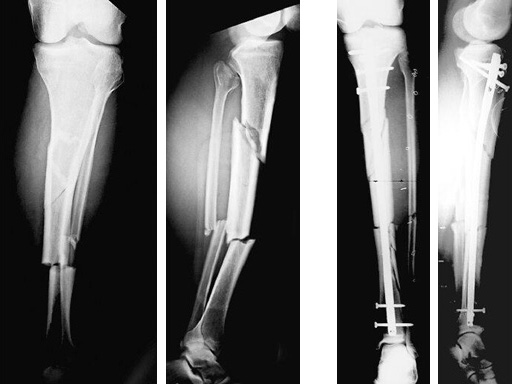

47-year-old man with closed 42-C3 fracture following a sports accident treated with ETNS.